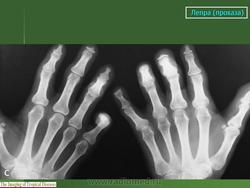

Рентгенологически специфические лепрозные оститы наблюдаются в виде (рис. 215) рассеянных множественных изолированных друг от друга очагов разрушения в корковом и преимущественно губчатом веществе эпифизарных и метафизарных концов фаланг, пястных и плюсневых костей. Реже они гнездятся в диафизах. Это резко очерченные округлые или чаще овальные просветления на месте рассасывания костной ткани бациллонесущей гранулойатозной тканью. Величина очагов в губчатом веществе колеблется от 2 до 8 мм в наибольшем длиннике, в корковом же веществе просветления меньше - до 3 мм в диаметре. Характерны весьма четкие контуры, окаймляющие костные изъяны.

Лепромы вызывают истончение коркового слоя, в результате чего могут возникнуть - надломы и переломы, не имеющие склонности к заживлению обычной костной мозолью. Очень характерны в окружности поверхностно расположенных гранулой периоститы малых трубчатых костей, вызывающие подчас даже некоторое вздутие кости. Г. Е. Живо-товский считает весьма показательным для этой формы проказы, т. е. для сочетания кожных и костных поражений, еще довольно резко выраженные муфтообразные оссифицирующие периоститы и остеопериоститы костей голени и в особенности- симметричные пластинчатые периоститы периферических отделов малоберцовых костей. 1Как известно, симметричные изолированные надкостничные наслоения именно этой локализации, т. е. на малоберцовых костях, не встречаются при других заболеваниях и поэтому приобретают известное диференциально- диагностическое значение.

Очаговое разрушение эпифизарных концов костей развивающимися лепромами влечет за собой также характерное изменение суставов, а именно подвывихи и вывихи, т. е. более или менее тяжелые деформации. Лепроматозные дефекты костей, по наблюдениям Г. Е. Животов-ского, отличаются стойкостью и при лечении не замещаются костной тканью.